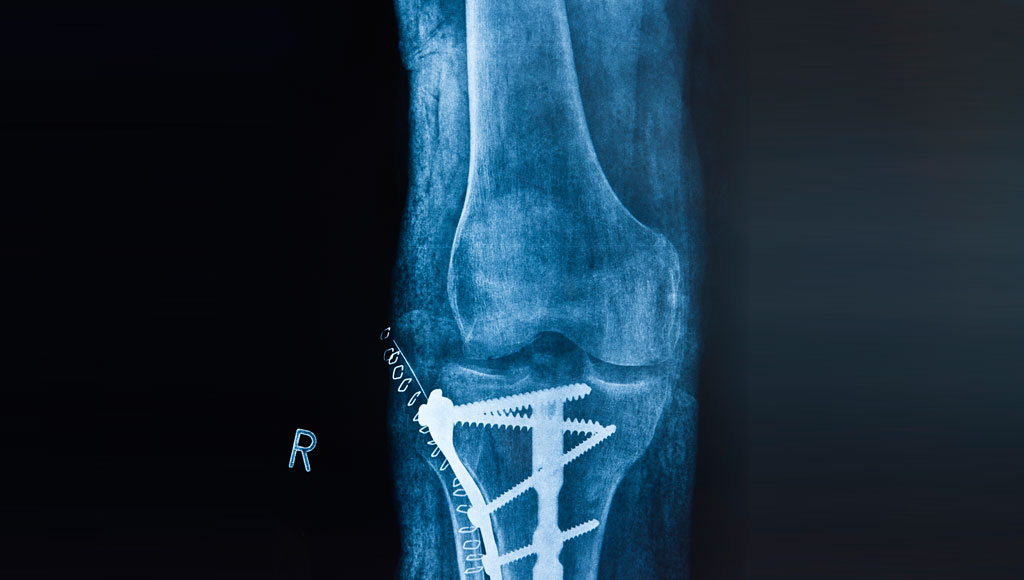

Post traumatic osteoarthritis occurs after there has been an injury or fracture in or around a joint. This could also include prior surgical procedures or even after surgery to correct a prior fracture. Post traumatic osteoarthritis occurs due to damage to the cartilage sustained from the injury. As with osteoarthritis the damaged cartilage is not able to heal and as time goes on the damage becomes more and more severe and eventually produces pain.

Post traumatic osteoarthritis is more difficult to treat than standard forms of osteoarthritis because there has been usually a significant injury which creates scar tissue formation along with increased complexity from any prior surgical procedures.

There may also be a need to remove any existing hardware in or on the bone and rarely the removal of the hardware may have to be performed by an orthopaedictraumatologist at the same time or at a different time than the total hip or total knee replacement.